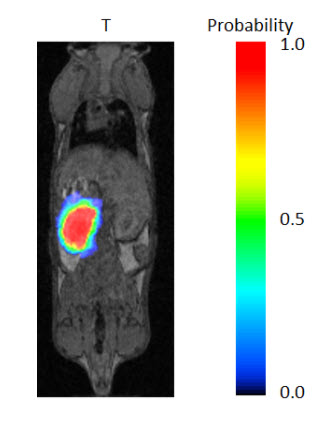

You can also edit the Probability Threshold. Following the registration of each Reference Image to the image in the Data Manager, each voxel is assigned a probability that it belongs in the ROI. Only voxels with a probability greater than the threshold you set will be mapped to the ROI. The default for this setting is 0.5; and, typically, the ROI will become larger as the threshold is lowered.